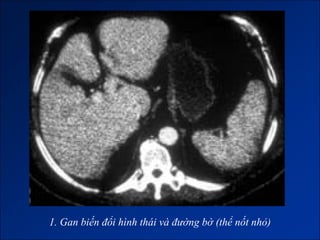

1. Gan biến đổi hình thái và đường bờ

1. Gan biến đổi hình thái và đường bờ (thể nốt lớn)

1. Gan biến đổi hình thái và đường bờ (thể nốt nhỏ)

Hình ảnh trên CLVT

- Giai đoạn sớm:

+ Gan to.

+ Tăng tỷ trọng do xơ hóa.

- Giai đoạn muộn:

+ Gan biến đổi hình thái và đường bờ.

+ Dấu hiệu tăng ALTMC.

+ Dấu hiệu khác:

Dịch ascite – Lách to – Dày thành TM.

Nốt tân tạo.

Biến chứng (HCC).